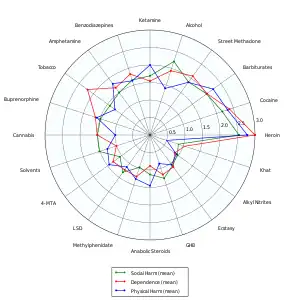

- ↑ Nutt D, King LA, Saulsbury W, Blakemore C (March 2007). "Development of a rational scale to assess the harm of drugs of potential misuse". Lancet. 369 (9566): 1047–53. doi:10.1016/s0140-6736(07)60464-4. PMID 17382831. S2CID 5903121.